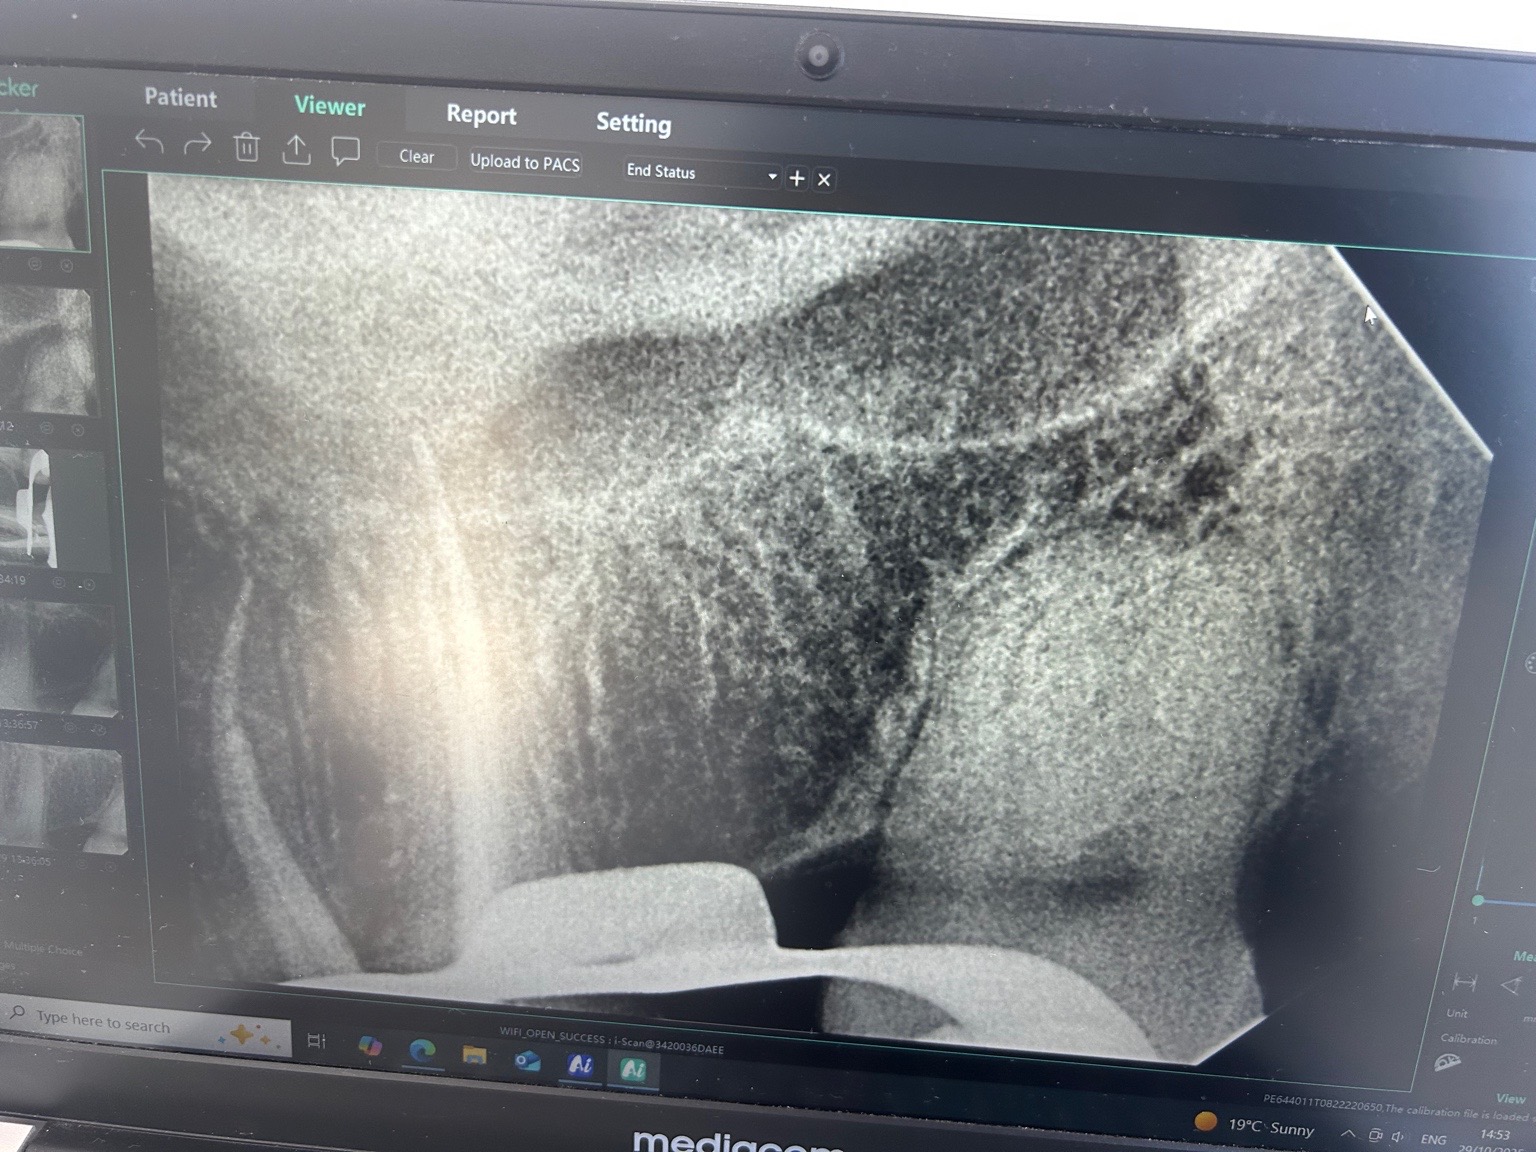

Initieel licht gevoelig aan kiezen. 1 maand. Koud alleen. Smeren tandpasta advies. Vorige week pijn. Diffuus moeilijk te pinpointen. Gevoelsmatige was het verstand kies. Daarna 6. Licht breuk lijn in 6 niet zichtbaar. Pijn 2 dagen. 1 dag diffuus kloppend. Koud test normaal. Foto gemaakt. Pijn trok weer weg. Geen wkb nodig. Afgelopen maandag test met bijt. 6 gevoelig met houten bijt test maar nog steeds geen beeld passend bij irreversible pulpitis. Tandarts vermoed sinus infectie op basis van deze foto. Gisteren en vandaag percussie gevoel weg na start behandeling neusspray. Pijn vandaag max. 1 tussen 1 en 10 2 tandartsen bekeken. Eentje niks over sinus andere wel. Helpt dit?

Om de sinus beter te bekijken zou ik een ander foto, een opt (panorama) willen hebben waarop de hele sinus te zien is en ook te vergelijken met de andere zijde. Op basis v deze foto is mogelijk een versluiering te zien maar zou dat zo niet in verband kunnen brengen met een sinusitis. Als u voorover buigt voelt u een klotsend gevoel in de neusholte.

Ik zie mogelijk een verbreed parodontaal spleet ( lijn tussen kies en tandvlees voor de leek) in de 25. Lijkt op een "diepe"vulling (dicht bij de zenuw)... hoe test de 25...Bij twijfel kan je eventueel proef boren zonder verdoving maar dat is niet altijd betrouwbaar. Knarst u??.

Tandarst vond de sluiering inderdaad een mogelijkheid, uiteraard niet definitief. Maar door koude test bijten op houten brokje zag hij niet echt een probleem met zenuw. k had wel sinus gerelateerde klachten. 2 a 3 weken geleden zware verkoudheid. Kreeg wel drukkend hoofdpijn. Klotsen gevoel neen, maar ik merkte wel druk gerelateerde perikelen maar negeerde ze. Focus was pijn :)